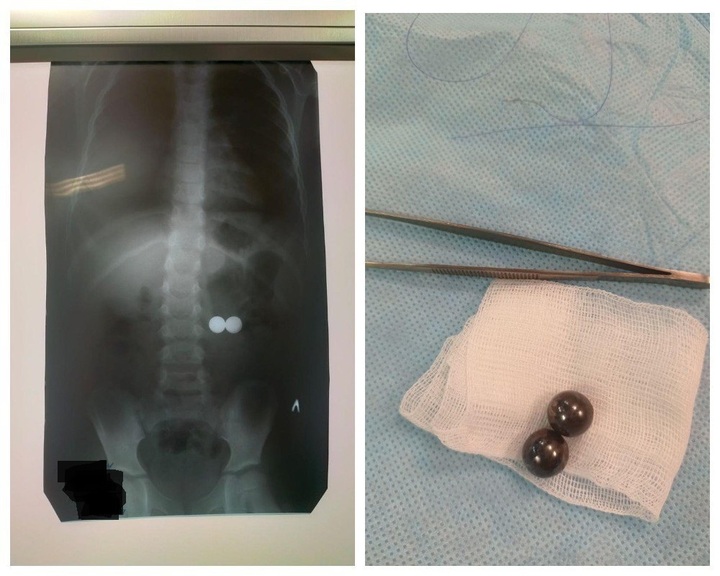

В Республиканскую детскую клиническую больницу были госпитализированы трое детей. Пятилетний мальчик проглотил два магнитных шарика, шестилетняя девочка — магнитный шарик и проволоку, а 13-летняя девочка — металлические бусины. Большинство инородных тел можно удалить эндоскопически, но магниты требуют серьёзного хирургического вмешательства. Благодаря оперативной помощи медиков детей удалось спасти. Теперь их ждёт длительная реабилитация.

В больнице собрали уже целую коллекцию предметов, извлечённых из дыхательных путей, ушей, носа и желудочно-кишечного тракта детей.